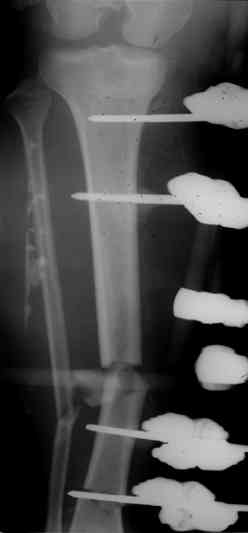

Больной 27 лет, мотоциклист. Поступил 23.04.10

ДЗ. О. перелом н.з левого бедра Gustillo 3b (c повредрение бедренной вены),

О.Правого бедра Gustillo 2, з. фрагментарный перелом левой голени.

При поступлении Hb 66 ISS 40, фиксация стержневыми аппратами, сосудистые хирурги выполнили шов вены. Выполена резекция бедренной кости 9 см

В настоящий момент планируем. Переход со стержневых аппаратов на стержни с антибактериальным покрытием на правом бедре и левой голени.

Вопрос: что делать с левым бедром? Учитывая внутрисутавной характер перелома, дефект бедра 9 см.